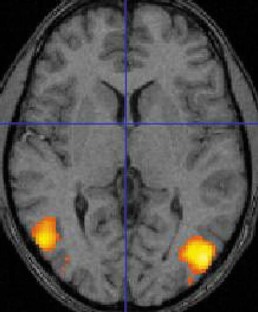

Extinction limited to visual motion perception in the left hemifield was demonstrated. The visual defect was attributed to a lesion involving the right occipito-temporo-parietal region in the presence of a left posterior infarction.

Fig 2